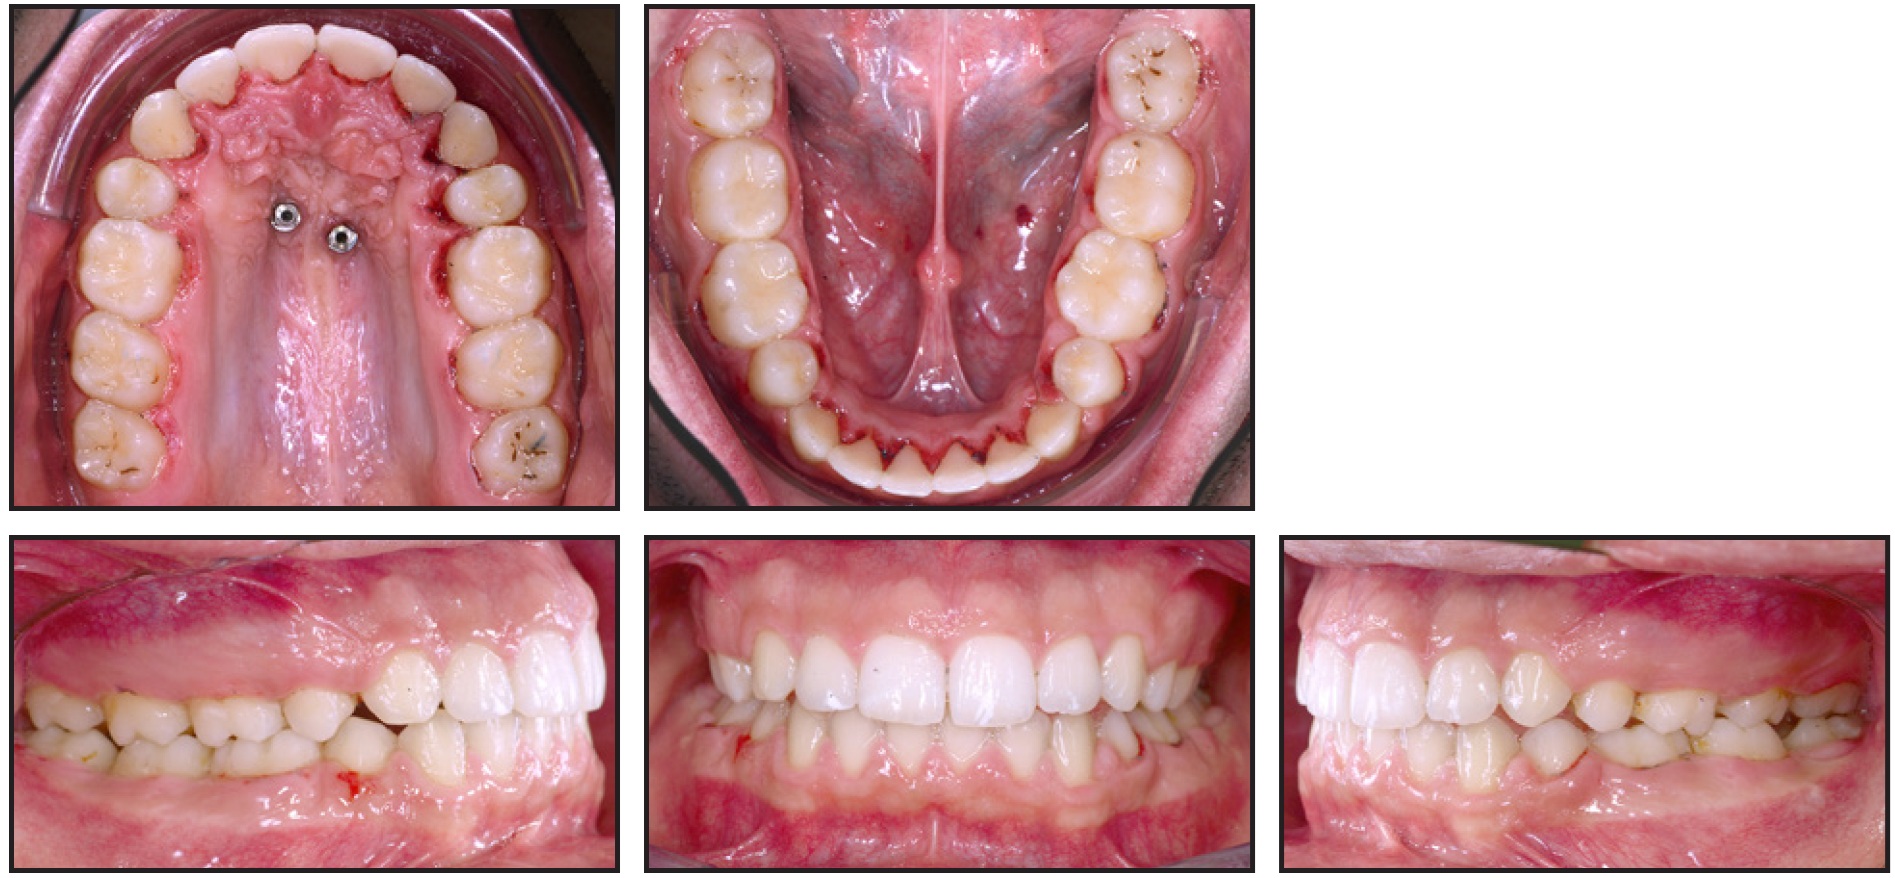

An 18-year-old male requested treatment with an esthetic appliance (Fig. 1). His profile was convex, with a balanced nose, normal nasolabial angle and mentolabial sulcus, and retrusive lower jaw. From the front, the face was well proportioned and symmetrical, with centered midlines, though a slight lip incompetence was noted.

Fig. 1 18-year-old male patient with gummy smile before treatment (continued in next image).

In smiling, the patient exhibited excessive gingival display, along with short clinical crowns, an interincisal diastema, and generalized spacing. Bilateral Class I canine and molar relationships were present, with mild crowding in the lower arch and exaggerated upper and lower curves of Spee. All teeth were present, including the third molars (Fig. 1B and 1C).